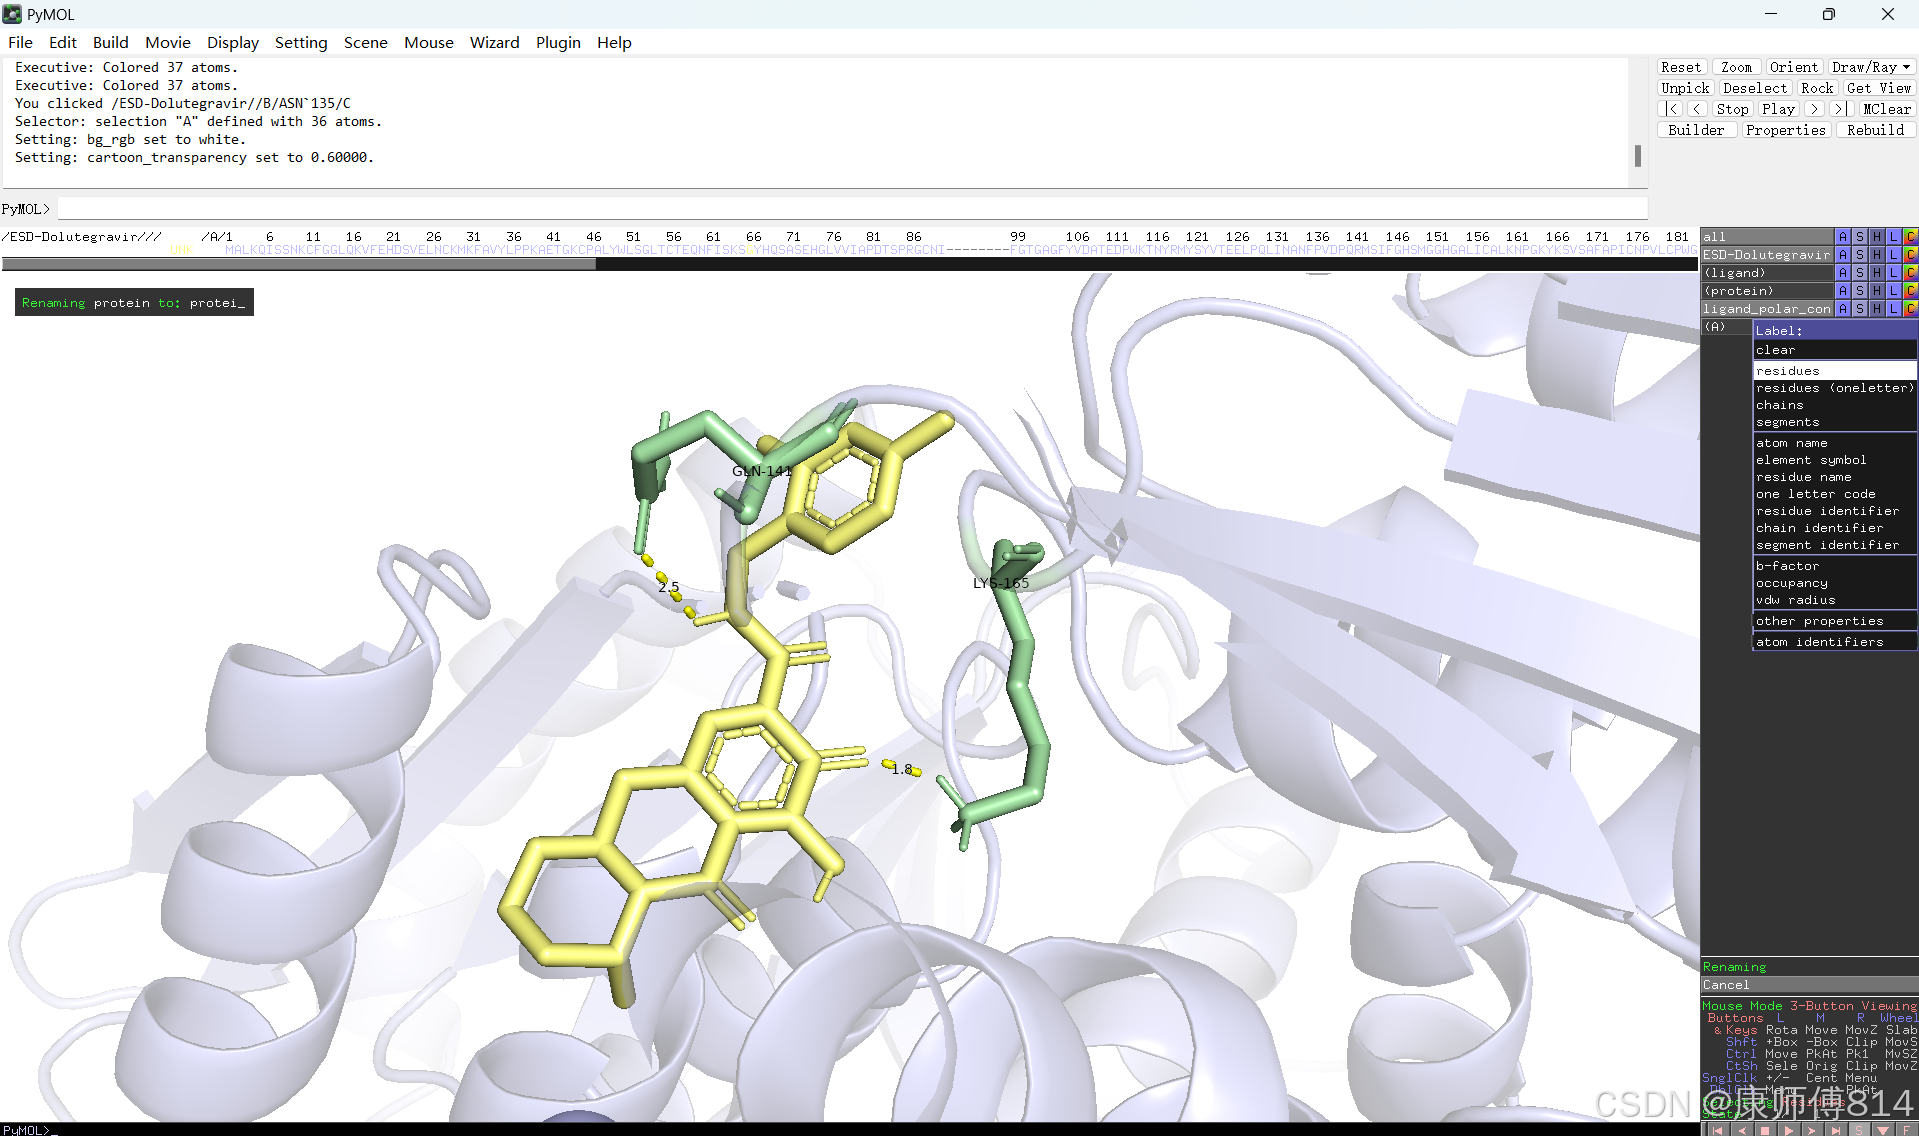

#选中小分子,按以下顺序点击以显示结合位点的氢键

#选中蛋白,点击show-sticks显示氨基酸棍状结构,右下角Selecting修改为Residues模式,选中与小分子连接的氨基酸残基,命名为A,并更改颜色

#点击蛋白,点击H-sicks隐藏蛋白棍状结构,然后显示小分子结合位点氨基酸残基棍状结构

#此时展示分子对接的基本要素已经形成,后续可根据需要修改背景颜色、显示氨基酸残基名字以及氢键键能等等,这里不再赘述

结果演示